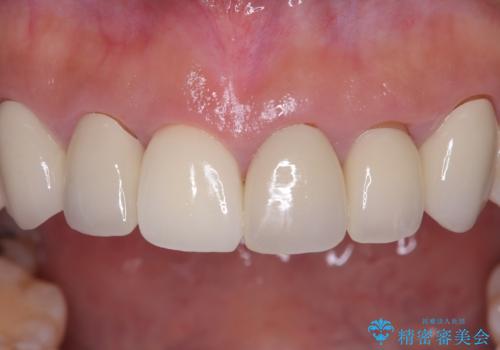

前歯の破折も1日で解決!抜歯即時インプラントで自然な笑顔へ

今回の治療では、まず原因となっていた前歯を慎重に抜歯し、その直後にインプラントを埋入しました。抜歯即時埋入は、歯を失うのとほぼ同時に新しい歯の土台を確保できるため、骨の吸収を防ぎ、仕上がりの美しさを保つ上で非常に有効です。また、治療当日に仮歯を装着することで、歯がない期間をなくし、患者様の精神的なご負担にも配慮しました。最終的に、周囲の歯と調和したオーダーメイドのセラミッククラウンを装着。機能性だけでなく、天然歯と見分けがつかないほどの自然で美しい前歯を取り戻していただけました。